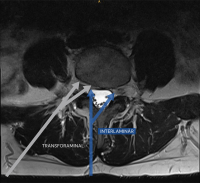

Zugangstrajektorie

Abbildung 5: Endoskopische Zugangstrajektorien der Lendenwirbelsäule: Die Abbildung illustriert die interlaminäre (blauer Pfeil) und transforaminäre (grauer Pfeil) endoskopische Zugangstrajektorie am Beispiel eines axialen T2-gewichteten MRI-Bildes der Lendenwirbelsäule. Der blaue Pfeil stellt den Zugang über das Interlaminärfenster dar, über welches ipsilateraler/kontralateraler Rezessus und zentraler Spinalkanal dekomprimiert werden können. Der graue Pfeil zeigt die transforaminäre Route zu extraforaminären, intraforaminären und intraspinalen Pathologien auf. Das chirurgische Risiko des interlaminären Zugangs der Brustwirbelsäule erhöht sich aufgrund der Lage des Rückenmarks deutlich, was die Anwendung im Bereich der Brustwirbelsäule limitiert.

Keywords: Endoskopische ZugangstrajektorieninterlaminärLendenwirbelsäuletransforaminärWirbelsäulenchirurgie